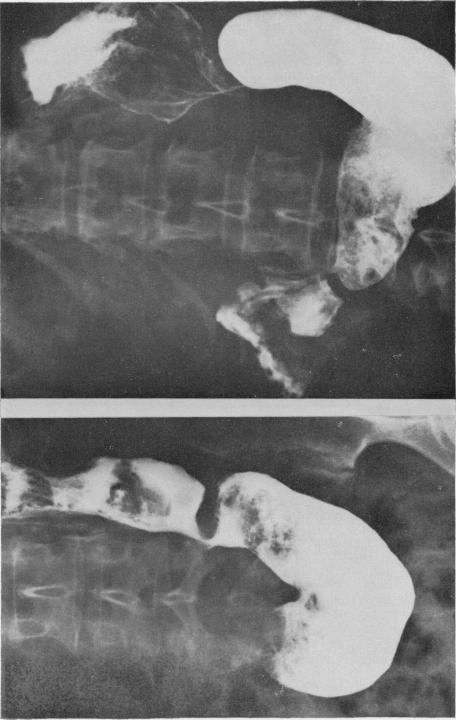

Hour-glass stricture of the stomach and iron deficiency.

Ulster Med J. 1966;35(1):50-71.